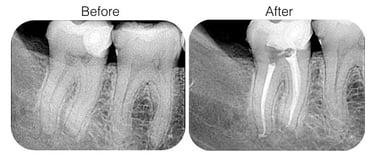

ROOT CANAL TREATMENT

Root canal treatment is a procedure to save a damaged or infected tooth by removing the infected pulp, cleaning and sealing the root canal. It relieves pain and prevents further infection, preserving the natural tooth.